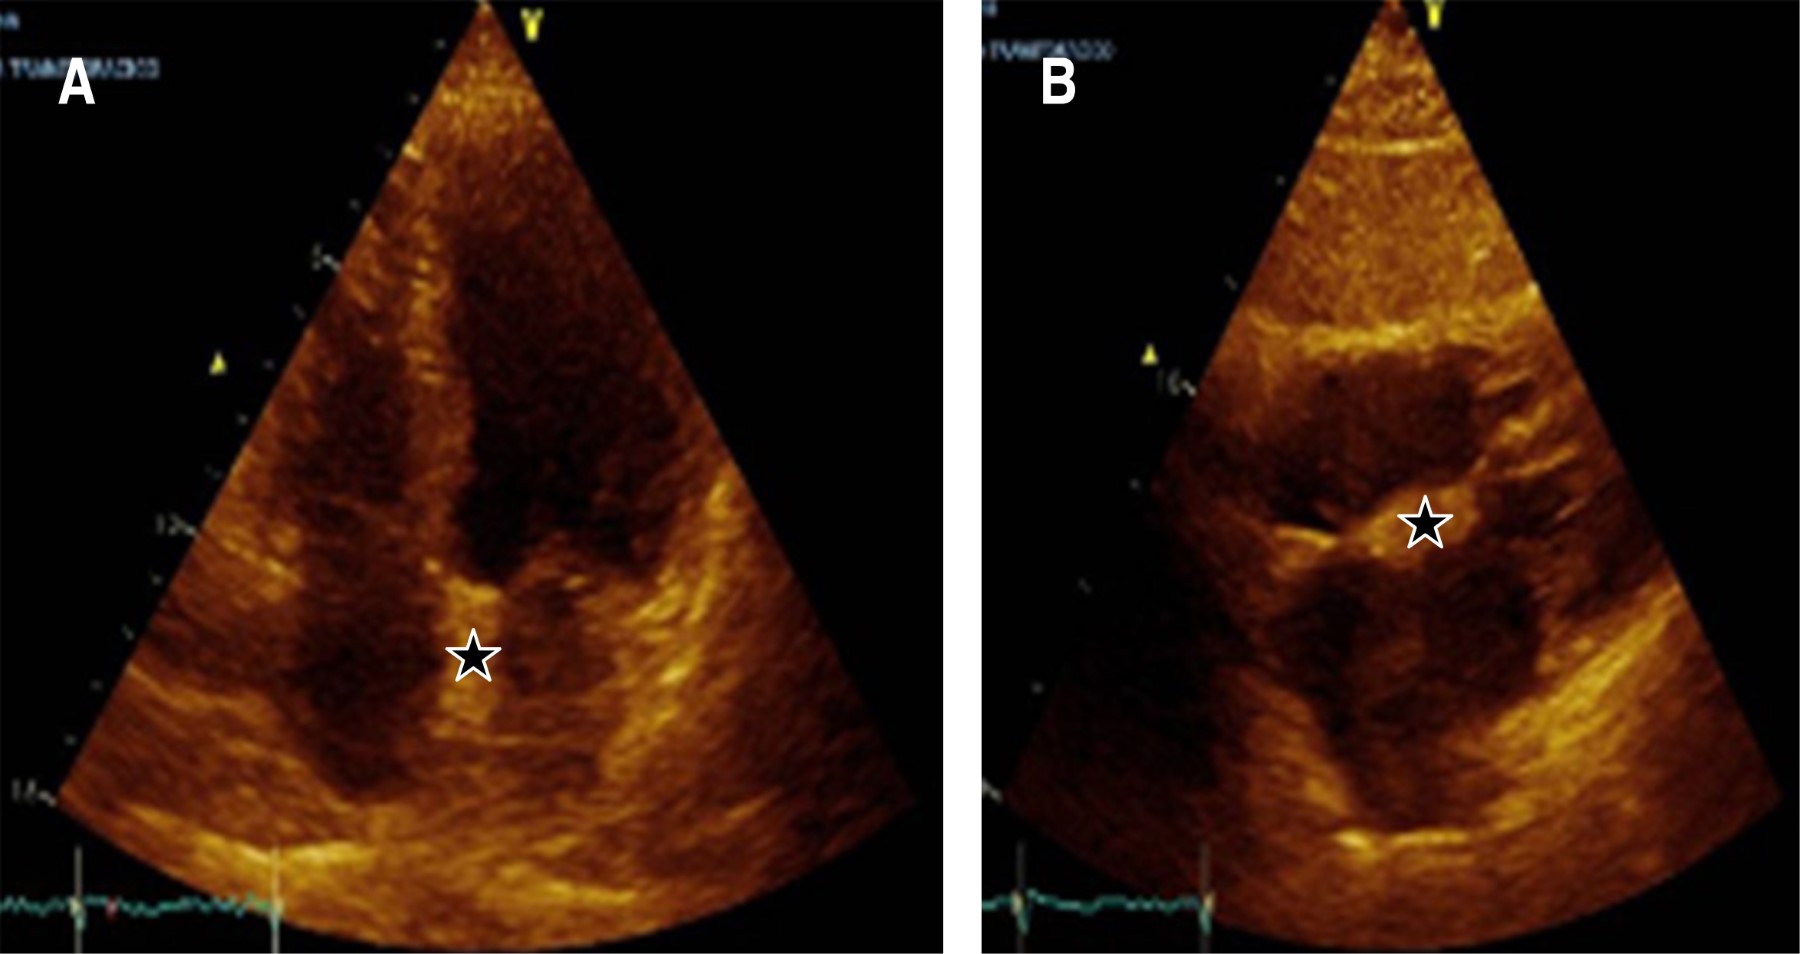

Palpitaciones como manifestación de hiperplasia lipomatosa del tabique interauricular: reporte de caso y revisión de literatura

La hipertrofia lipomatosa del tabique interauricular se reconoce cada vez más y debe considerarse como parte del diagnóstico diferencial de uier tumor cardiaco. Presentamos el caso de un paciente de 70 años que acudió al servicio ambulatorio por palpitaciones. El ecocardiograma transtorácico (ETT) detectó engrosamiento del septo interauricular de predominio proximal con respecto de la fosa ovalis. El diagnóstico fue confirmado por resonancia magnética cardiaca. En tales casos, la opinión de un cardiólogo experto en imagen cardiaca ayudaría a evitar un diagnóstico erróneo y una intervención innecesaria. Esta condición es más común de lo que se pensó inicialmente y sigue siendo poco reconocida por la mayoría de los médicos.

Figura 1